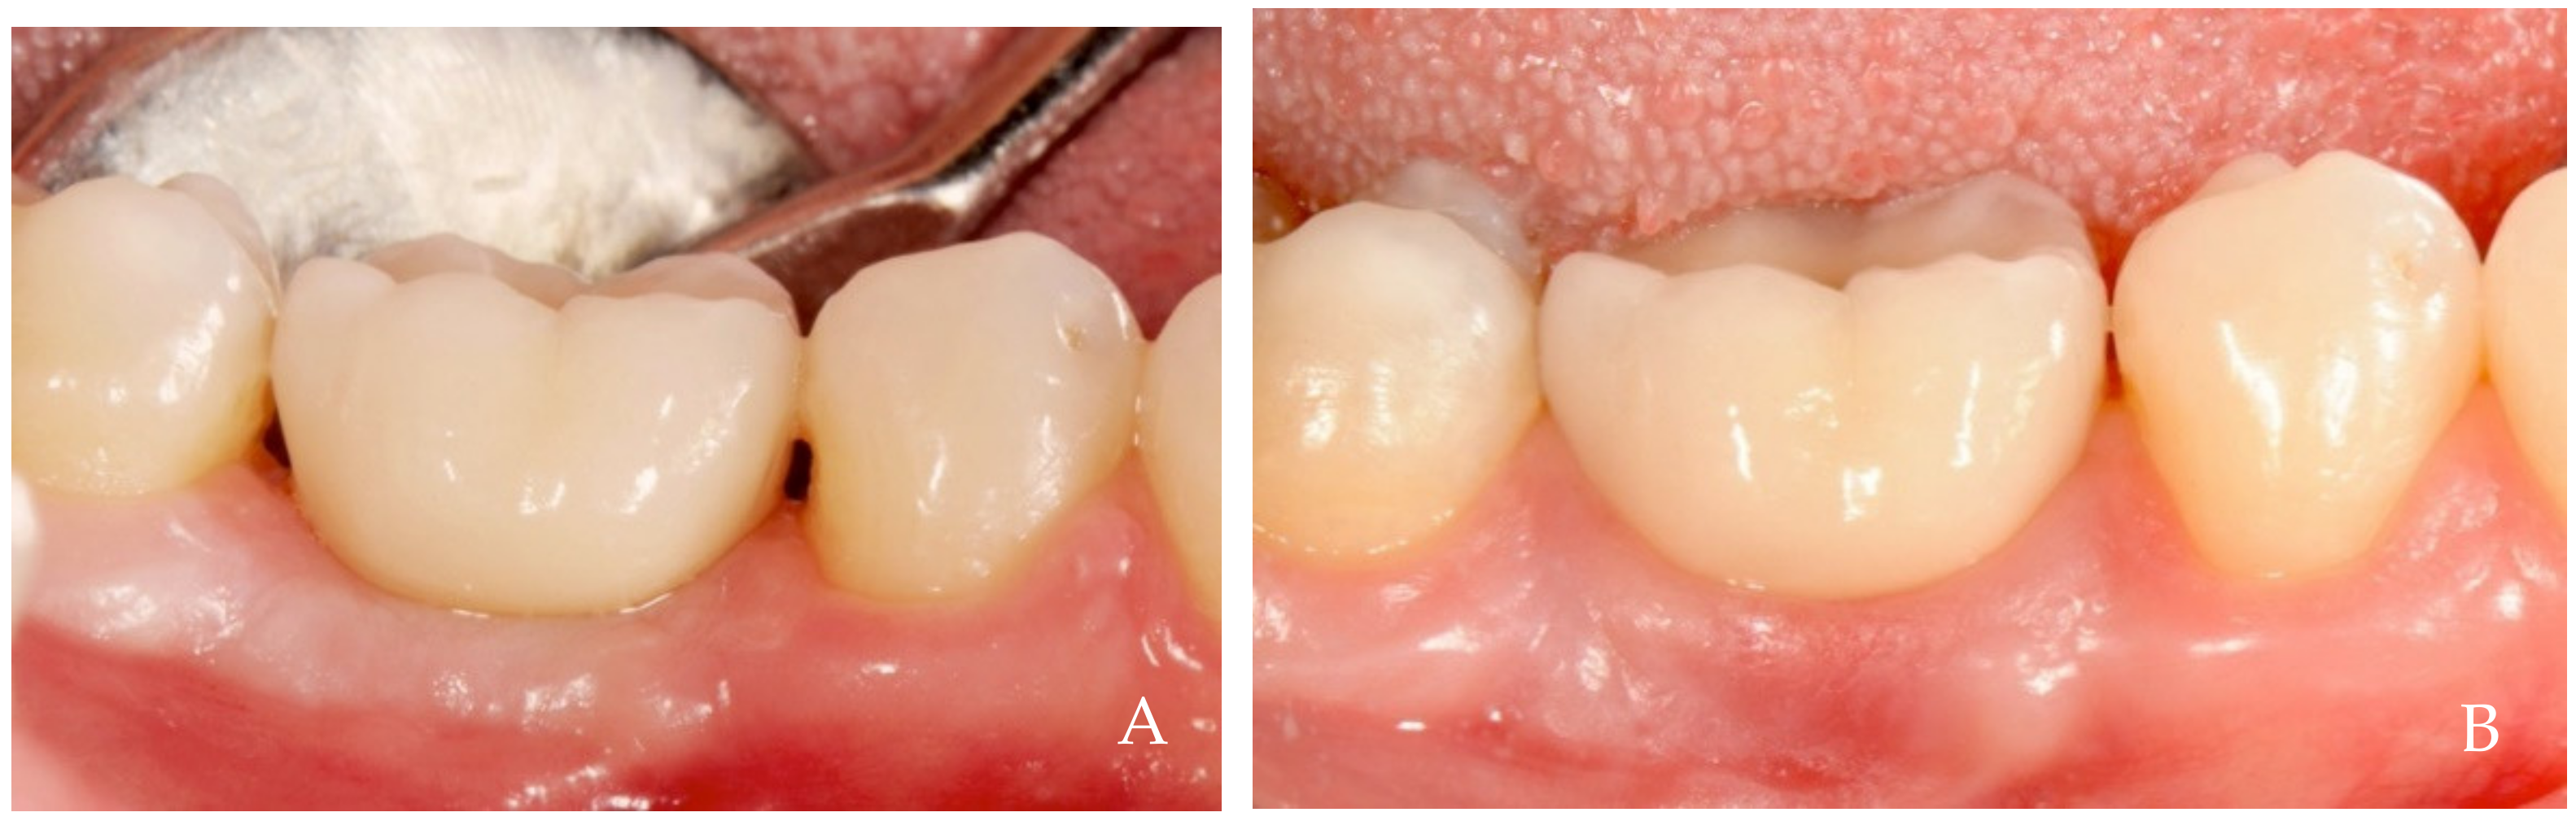

2. Clinical Examples of Oral Soft Tissue Growth